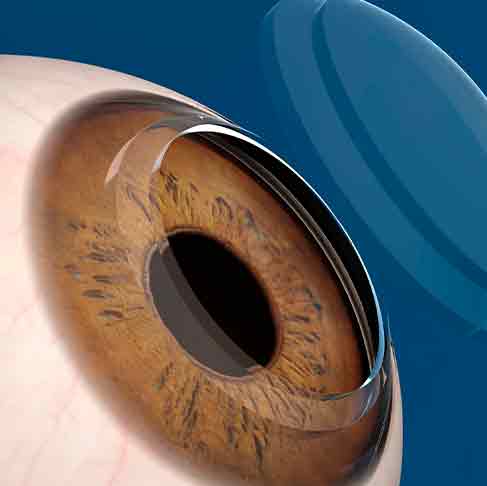

Transplante de Córnea

O Transplante de Córnea é um procedimento cirúrgico que substitui uma parte ou a totalidade da córnea doente ou danificada por uma córnea saudável de um doador. Algumas causas comuns que podem trazer a necessidade de transplante de córnea são o ceratocone e outras doenças ectásicas da córnea, cicatrizes devido a infecções ou lesões, degenerações e distrofias corneanas e complicações de cirurgias oculares anteriores.

O transplante de córnea é realizado sob anestesia local ou geral, dependendo do caso. O cirurgião remove a córnea doente e a substitui pela córnea do doador. Após o transplante, os pacientes geralmente precisam de várias semanas a meses para se recuperar completamente. Durante esse período, é importante evitar atividades que possam prejudicar os olhos.